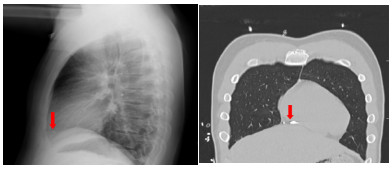

心脏内异物临床少见,通过外周静脉移动至心脏内的异物更是罕见[1-2]。本文报道了1例一枚金属异物从左前臂刺入进而随静脉血流移动至右心室,并通过此病例对心脏内异物的临床诊治予以归纳总结。

2.3 治疗目前,心脏异物的诊治仍无标准化指南。在异物迁移到心脏的情况下,已经提出了几种治疗方法。如患者无不适主诉,可进行临床及X线随访[15, 20-23]。如患者有不适症状或异物直接威胁到心血管完整性,则行手术移除。手术方式包括胸廓切开术或胸骨切开术,伴或不伴体外循环[24-30]。Legras等[31]提出心脏异物的诊疗思路(图 5)。部分患者对心脏异物的存在感到焦虑,这也是手术的绝对指征[32-34]。Symbas等[8]认为腔内或部分嵌入心肌的异物,特别是左侧心腔,因感染或栓塞的风险而应移除。一些医源性的异物因涉及医疗法律纠纷,有时会影响手术或保守治疗的选择。